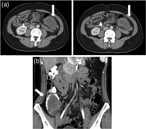

Infiltrating caecal carcinoma versus appendicitis with caecal phlegmon—can computer tomography differentiate them?

Henry To and others

Journal of Surgical Case Reports, Volume 2017, Issue 2, February 2017, rjx006, https://doi.org/10.1093/jscr/rjx006